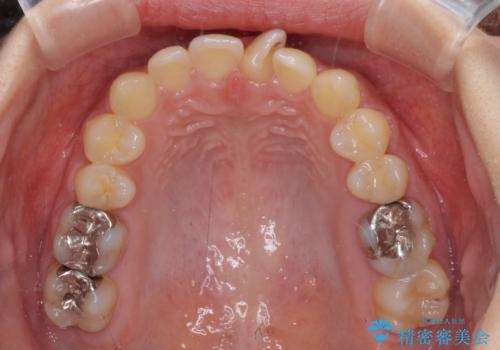

深い咬み合わせとデコボコの歯列をワイヤー矯正で改善

- 前歯のデコボコと深い咬み合わせを改善したいとのことで来院された患者様です。

奥歯の咬み合わせは上顎に対して下顎が後方位にあり、上顎前歯で下顎前歯が隠れるような典型的な過蓋咬合です。

補助装置を用いて上顎大臼歯を後方に移動させながら、ワイヤー装置で歯列を整えて深い咬み合わせを挙上することとしました。